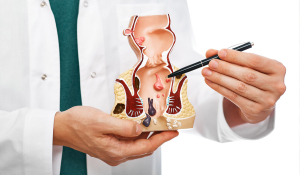

Гемороїдектомія у Івано-Франківську